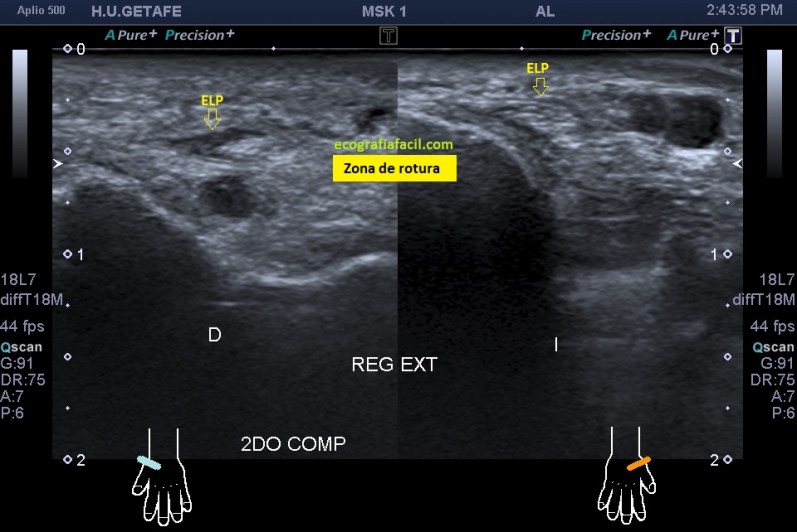

Seguimos avanzando hacia distal, seguimos observando las mismas diferencias en las imágenes comparativas. Imagen justo antes de la rotura.

En la rotura el tendón es muy pequeño, pero normal en la izquierda y en la derecha lo es igual de pequeño, pero aplanado y con la pérdida de la ecogenicidad normal.